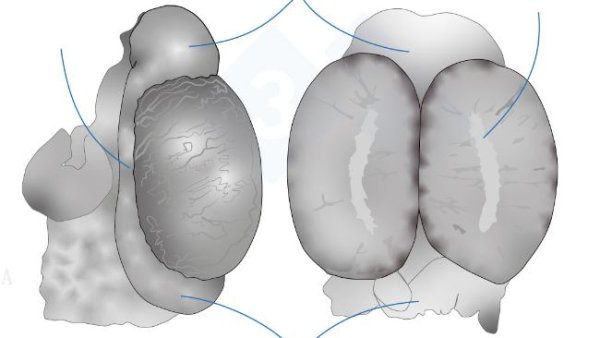

En esta segunda entrega vemos la extracción del conjunto lengua-tráquea-pulmones-corazón. Extraeremos los órganos de la cavidad abdominal, tanto del sistema digestivo como del aparato urinario y genital. En la cabeza accederemos a los cornetes nasales y el cerebro y cerebelo.